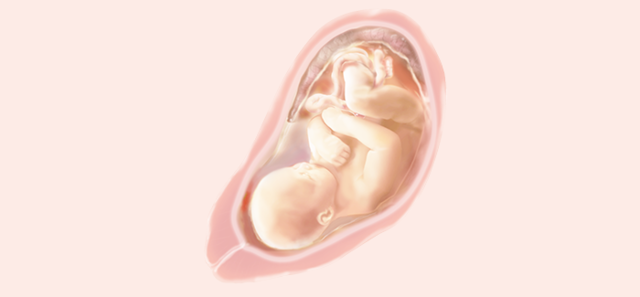

Tu hijo flota en el agua, ya que todavía el saco amniótico es muy espacioso. Esto permite al bebé moverse de un lado a otro, darse la vuelta, girarse, dar patadas y cambiarse de posición varias veces en un día

• SEMANA 25

SEMANA 25

Pesa ya 700 gramos y mide 22 centímetros desde la cabeza al final de la columna ( cráneo-caudal).

Los párpados del niño se abren y se pueden ver los ojos. La lengua sale de la boca y se mueve hacia los lados. Tu hijo bosteza, sonríe y empieza a hacer gestos como si de un niño mayor se tratase